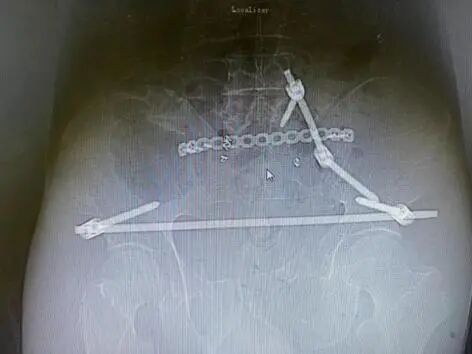

目前骨盆前环骨折的固定方式主要有四种:钢板、螺钉、外固定支架、内固定支架(即Infix技术)。由于前三种手术技术存在一定局限性,学界一直在寻找一种更加安全可靠、操作简单的骨盆前环骨折固定技术。

2009年:Kuttner研发了一种基于经皮下骨盆前环内固定技术(internalfixator, INFIX),用于耻骨联合分离的复位与固定,后续所有24例患者,术后复查复位均良好。

2012年:Vaidya详细阐述并明确提出了Infix的观念:Internal fixator适用于前环损伤的骨盆骨折,尤其是肥胖、伴有膀胱损伤的患者。

该手术在皮下操作,在超髋臼区进行固定稳固,具有力臂短、把持力强、操作简单、创伤小、容易取出、允许早期锻炼及负重、不需要考虑血管神经等优点,更符合BO原则。